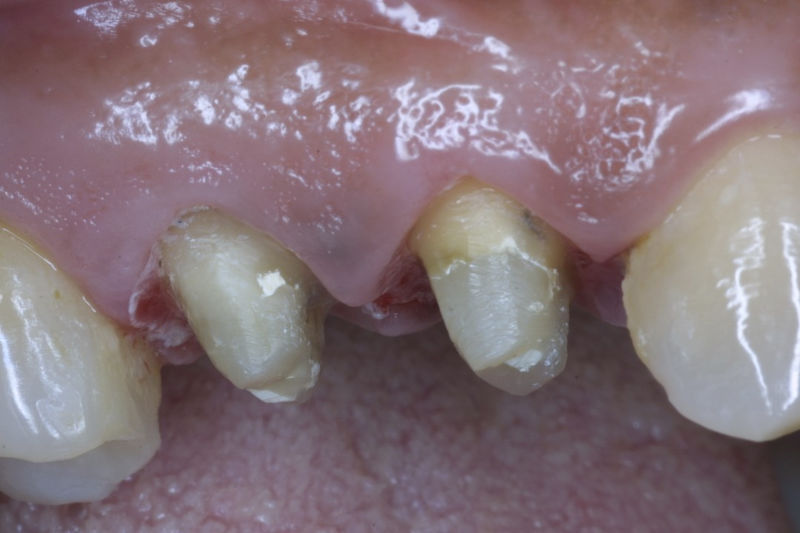

Restauraciones fabricadas en el laboratorio con materiales estéticos, los cuales cubren de manera total dientes anteriores y posteriores. Se utilizan primariamente para restaurar dientes con caries, fracturas y/o defectos amplios, así como soportes de puentes. Para poder enviar el caso al laboratorio se toman impresiones utilizando materiales de impresión o técnicas modernas digitales.